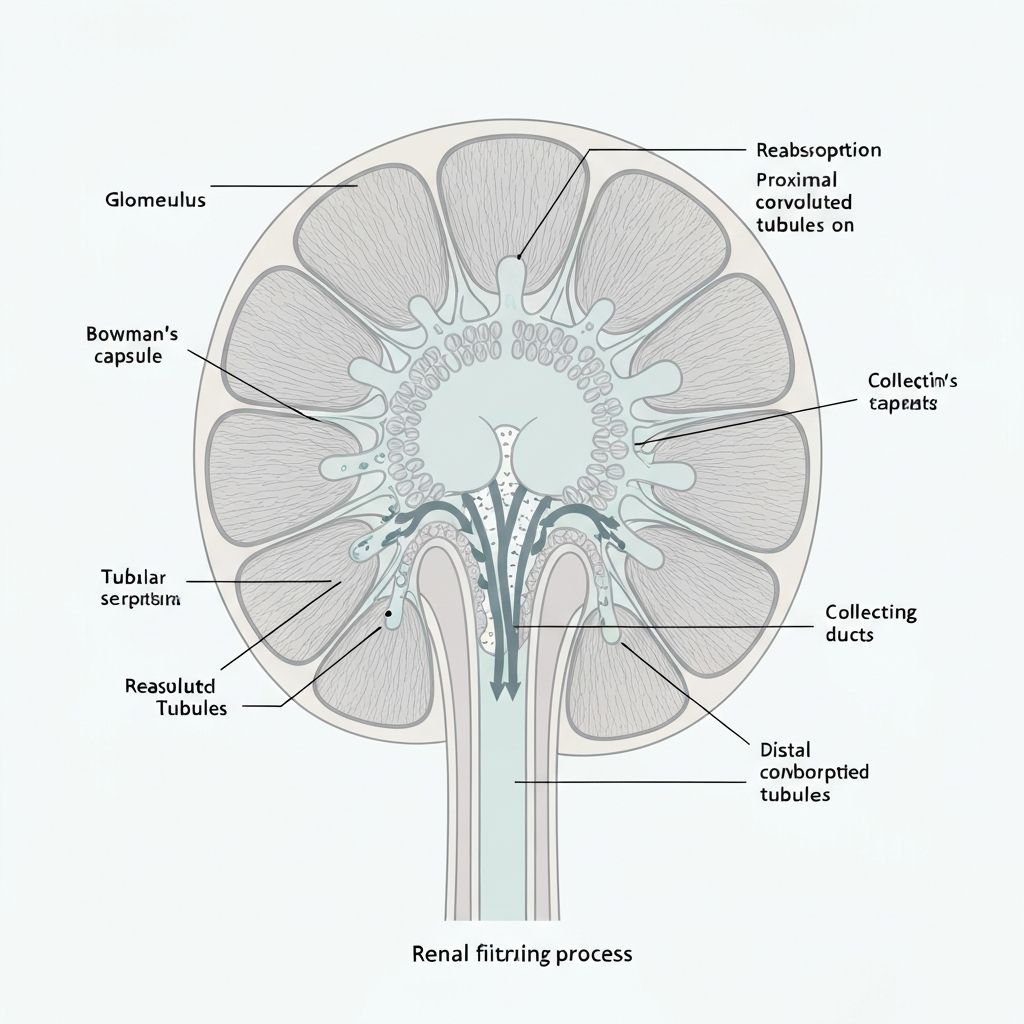

Renal Filtration and Excretion

The kidneys maintain body fluid balance by filtering water-soluble metabolites from the bloodstream. This occurs through:

Glomerular Filtration

Small molecular compounds are filtered passively from the blood through the glomerular membrane, creating the primary filtrate.

Tubular Reabsorption

Essential nutrients and electrolytes are selectively reabsorbed as the filtrate moves through the renal tubules.

Tubular Secretion

Additional metabolic waste is actively secreted into the tubular fluid for elimination.

Read the detailed physiological explanationRenal Excretion

How kidneys filter and eliminate metabolic byproducts from the bloodstream.